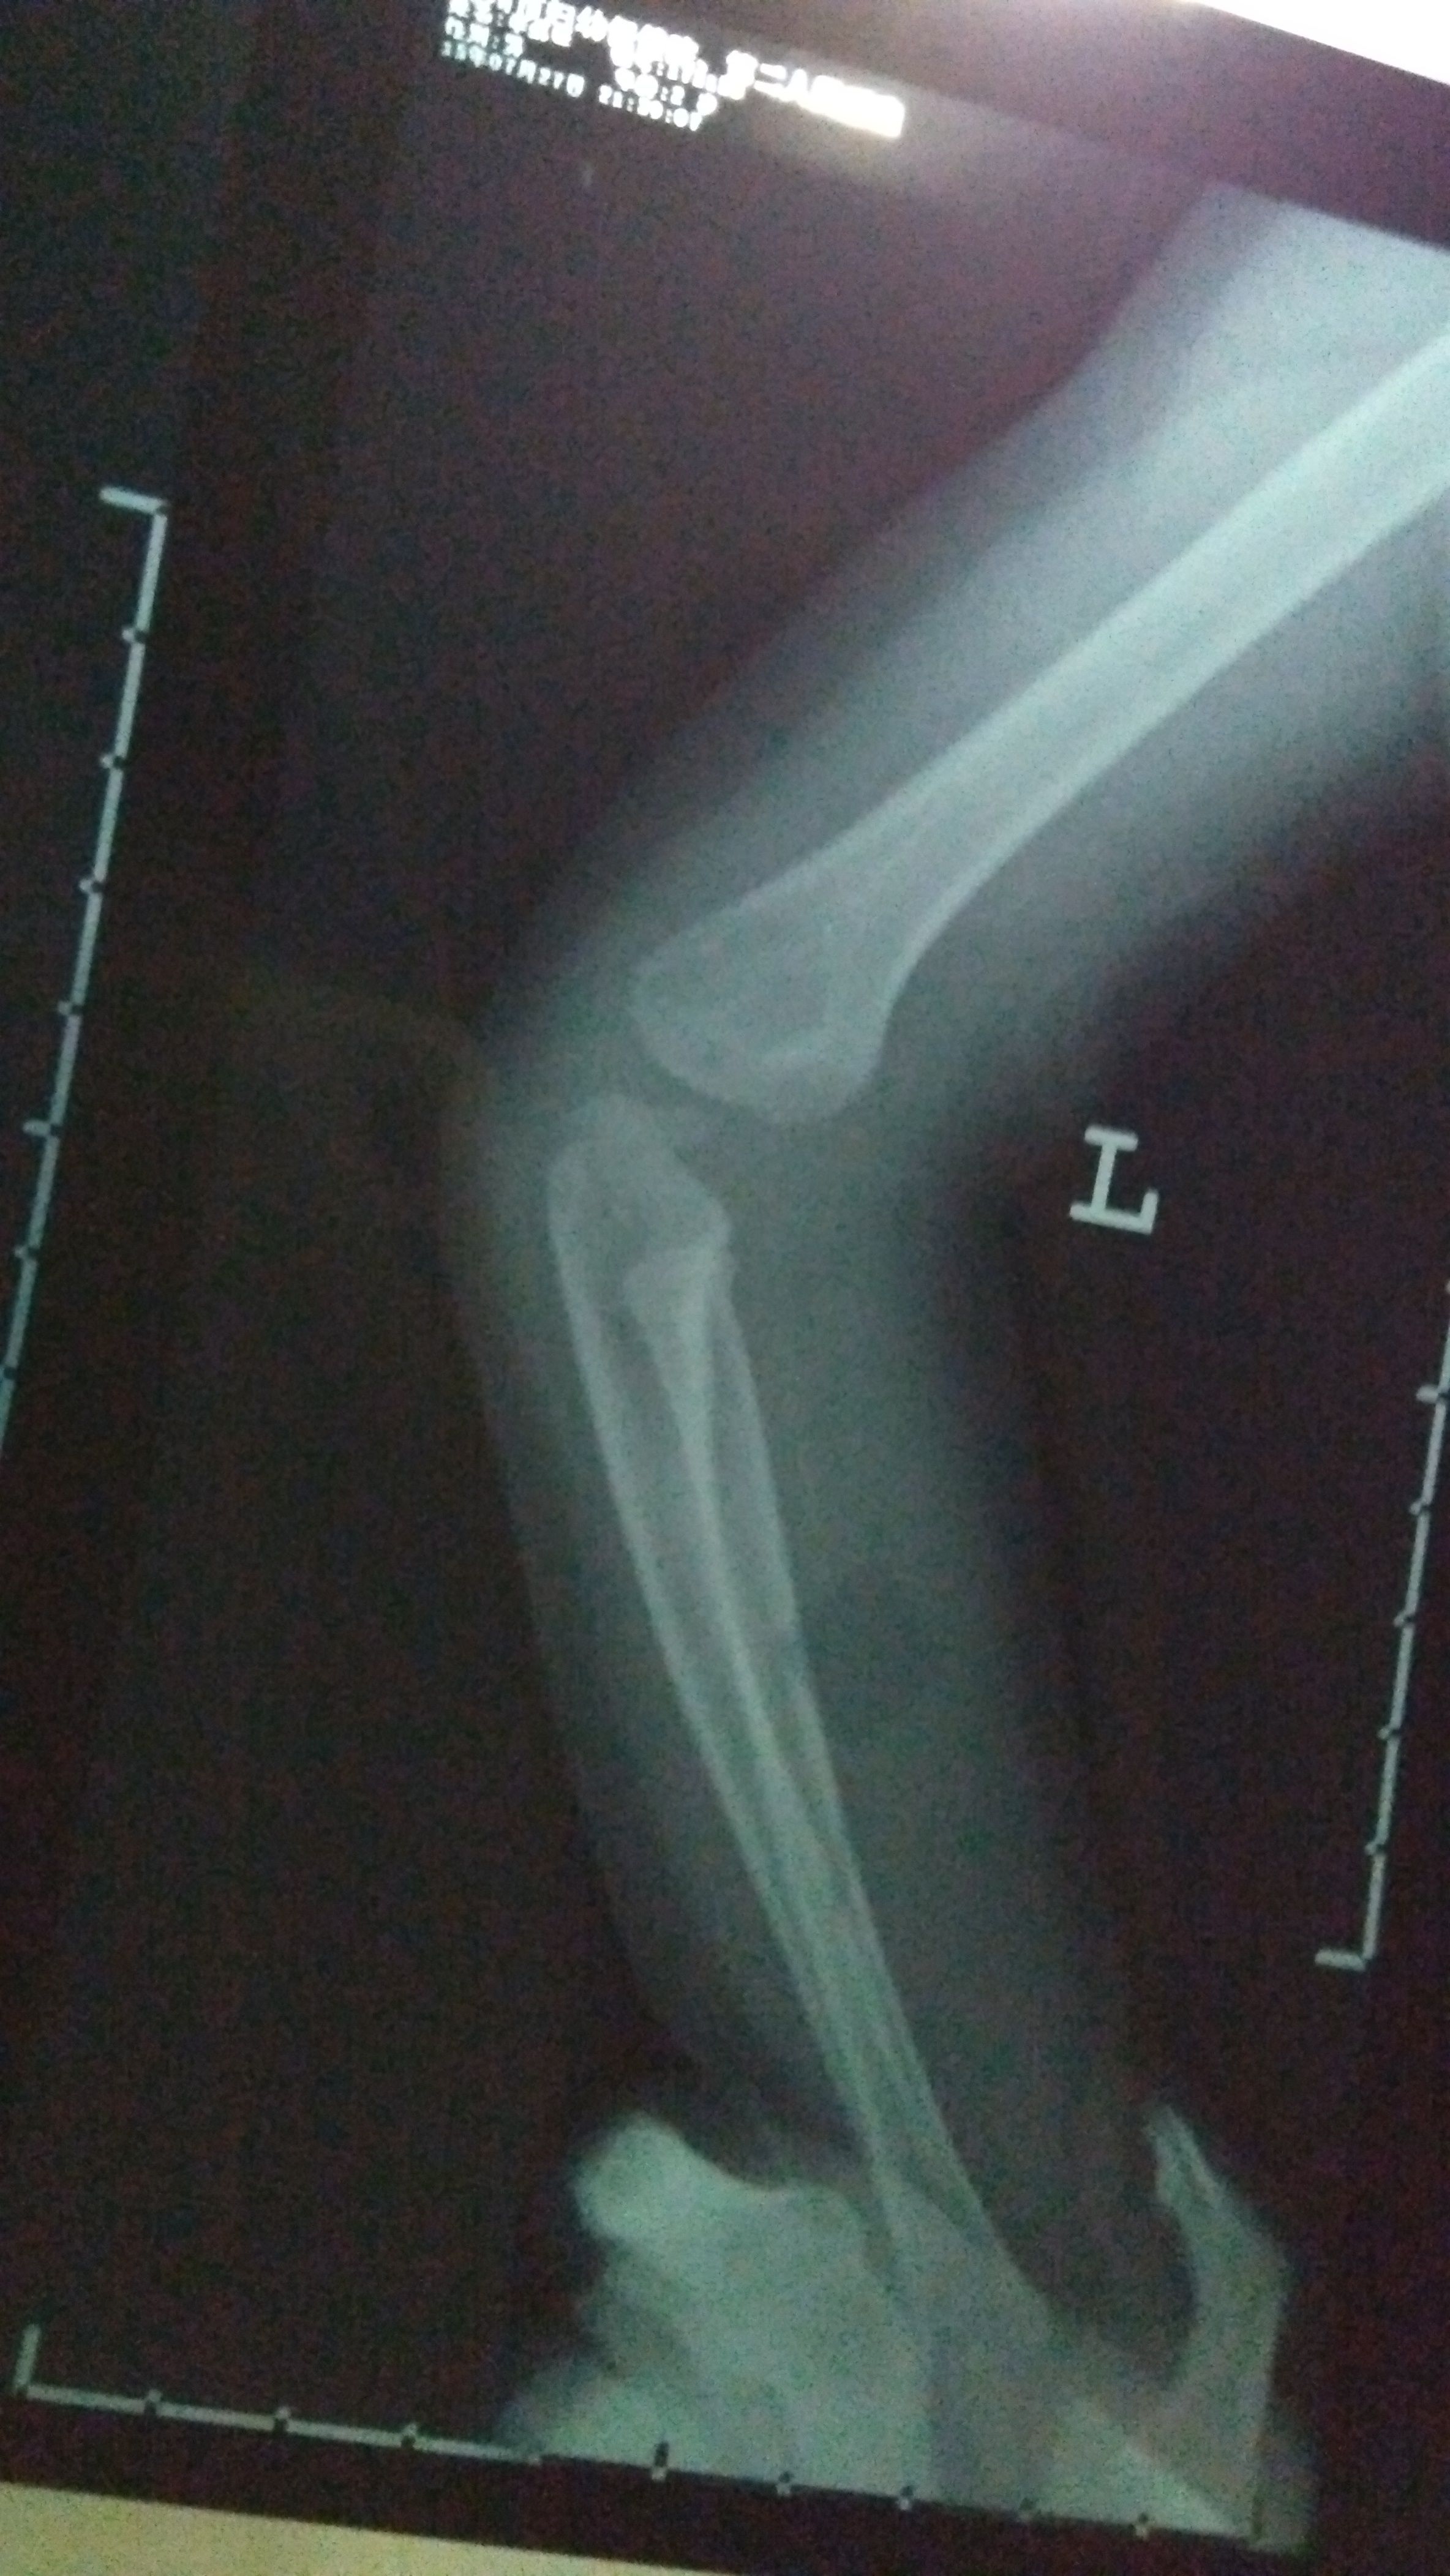

2岁宝宝骨折,急急急! 宝宝今晚玩耍奔跑时,摔倒姿势有异(速度很快不小心扑倒了,整个左手臂压在他自己身下,当时就骨折了)。 宝宝一直出冷汗表情痛苦哭,左手不动弹,我们赶紧去医院。以下是X光片(左手)和报告,打了石膏,医生让4-7天内去复查。 另外医生说小儿骨折这个部位骨垢骨折的情况比较少见,需要我明天带着片子报告去给他们主任看一下,看是否会影响手臂的功能性。如果有功能性影响,会影响孩子发育,还得纠正,做手术。 我知道医生总是会预先把最坏的结果告知患者,可是伤在儿身,痛在娘心。我担心害怕要做手术,加上回家后老公一直在说医生当时石膏没打好,让我带宝宝明天去重新打过石膏…说医生不太靠谱。确实,那个医生打石膏的时候还在接电话,一直不停跟他家人打电话接电话。 恳求有懂小儿骨折的医生帮帮我,看看我宝宝这个情况到底怎样?会影响他发育吗?可能要做手术纠正吗?跪求了!万分感谢!

这个部位骨折是非常清楚的,先打石膏固定一下(不可重复打石膏),看看恢复情况,如果效果不好一周之内要手术治疗!